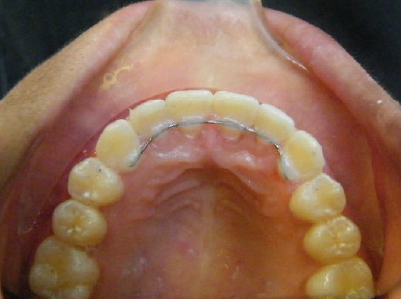

Patient 2: Significant increased overjet and upper and lower crowding.